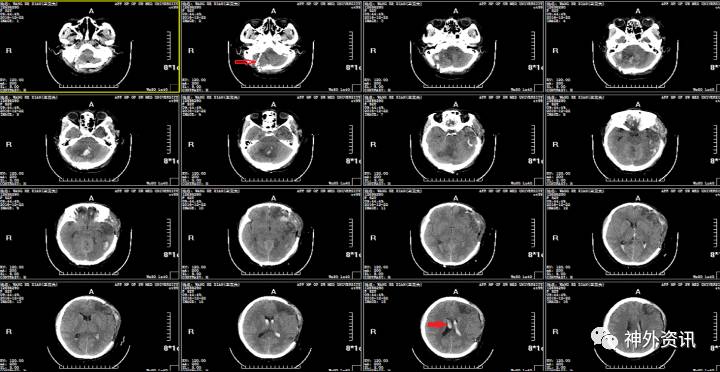

空心箭头:血浆引流管;实心箭头:脑室积血。

2016.12.21:患者生命体征平稳,自主呼吸,意识呈浅昏迷,双瞳不等大,左瞳直径3.0mm,右瞳2.5mm,光反射均迟钝,复查头颅CT示:环池欠清,脑室积血,脑组织稍肿胀,未见明显脑积水,暂不考虑手术,予以止血、脱水、促性、预防感染及癫痫处理,动态头颅CT密切监测患者病情变化。

2016.12.24:患者意识仍昏迷,双瞳等大形圆直径约2.0mm,光反射迟钝,复查头颅CT发现脑室系统积血存在,三脑室及侧脑室明显扩大,考虑脑室积水,在急诊局麻下行:右侧脑室外引流术,考虑患者短时间内不能清醒,予以气管切开处理。

2016.12.25:侧脑室外引流术后第1天复查头颅CT,脑室系统积血明显减少,脑室大小恢复。继续予以脱水、促醒、预防感染等对症支持治疗,血浆引流管爬坡10cm,密切观察患者病情变化。

箭头为脑室引流管

2017.01.03:侧脑室外引流术后第10天,患者意识呈昏睡,生命体征平稳,脑室引流管通畅,引流清亮脑脊液140ml,双瞳等大形圆直径2.5mm,光反射迟钝,予以关闭血浆引流管48h后复查头颅CT。

2016.01.06:复查头颅CT,关闭脑室血浆引流管后无脑积水表现,予以拔除血浆引流管。